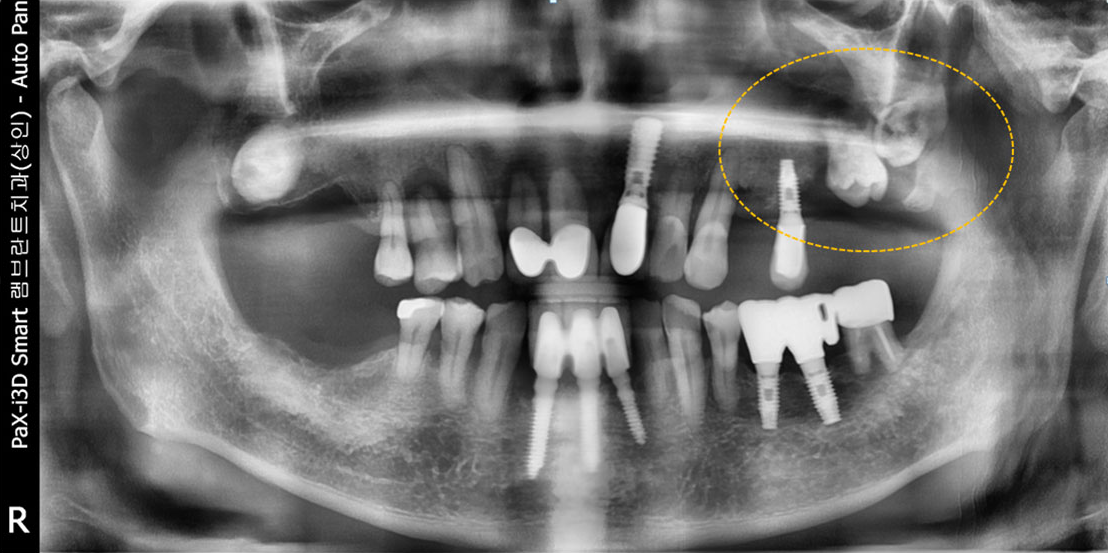

타 치과의 뼈 이식 후 골조직

램브란트치과 상인점 뼈이식 후 골조직

상악동 공간이 내려앉은 경우

윗턱뼈의 두께가 얇은 경우

아래턱뼈의 두께가 얇은 경우

윗턱뼈에 사랑니가 매복된 경우

신경관과의 거리가 부족한 경우